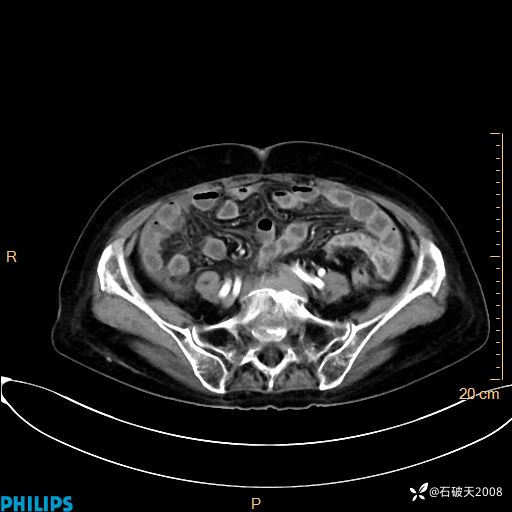

静脉期